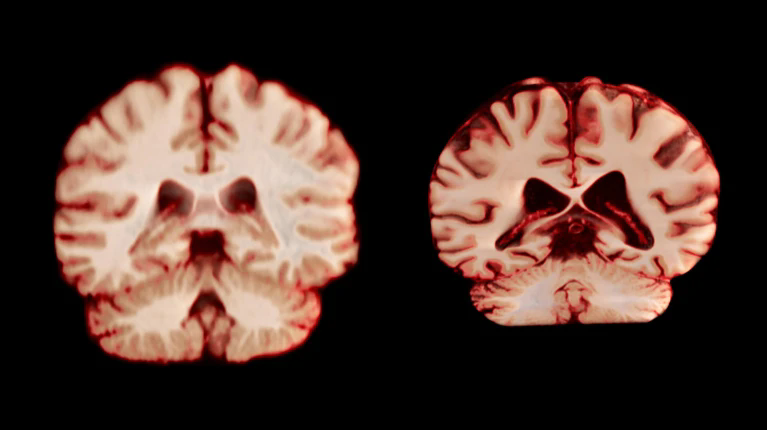

健康大脑(左)和患有阿尔茨海默病的大脑。图片来源:Anatomical Travelogue/SPL

男性大脑萎缩速度快于女性,与老年痴呆有何关系。10月13日,一项发表于美国《国家科学院院刊》的纵向研究指出,在衰老过程中,男性大脑多个区域的体积缩减幅度大于女性。研究者认为,这一结果意味着,与年龄相关的大脑变化并不能解释为何女性被诊断出阿尔茨海默病的概率高于男性。